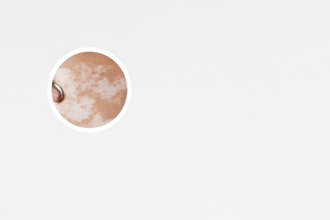

照光后白斑變紅是一種正常的反應(yīng)。照光治療可以促進(jìn)患者患處皮膚的血液循環(huán),增加色素細(xì)胞的活力,從而改善白斑情況。白斑變紅意味著皮膚血液循環(huán)得以恢復(fù),病變區(qū)域的色素細(xì)胞功能有所改善。因此,患者不必過于擔(dān)心,可以繼續(xù)進(jìn)行照光治療。

其特點(diǎn)是皮膚出現(xiàn)白斑,因?yàn)樯丶?xì)胞受損或功能異常導(dǎo)致。照光治療是一種常用的非藥物治療方法,通過在患處照射特定波長的光線來刺激色素細(xì)胞的活力,促進(jìn)色素生成,改善白斑。

照光后出現(xiàn)的紅斑可以分為兩種類型,一種是正常的生理反應(yīng),另一種是病理性反應(yīng)。正常的生理反應(yīng)是指照光后皮膚局部出現(xiàn)紅斑,但不伴有其他不適癥狀,這通常是因?yàn)楣饩€刺激導(dǎo)致的血液循環(huán)加快所致,是正常的治療反應(yīng),不需要停止照光。而病理性反應(yīng)則是指照光后紅斑伴有疼痛、瘙癢、腫脹等癥狀,可能是治療過程中出現(xiàn)了問題,建議及時(shí)就醫(yī)咨詢。